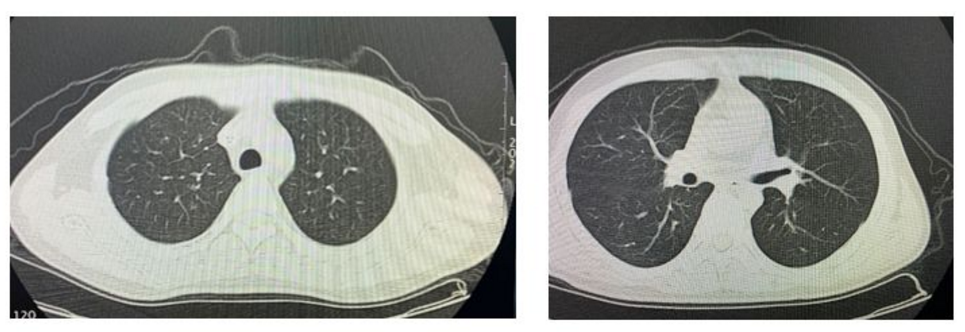

2020.1.16患者剛入院行胸部CT檢查顯示

2020.3.9患者治療后行胸部CT檢查顯示

由于巨細胞病毒肺炎的早期診斷,我們及時給患者應用更昔洛韋的抗病毒治療,同時結合丙種球蛋白輸注提升免疫力,并給予臍帶間充質干細胞5u/周,連續4周輸注,調節免疫,減輕炎癥因子所致的免疫肺損傷。患者2周后影像學明顯改善,磨玻璃影大部分吸收好轉,沒有遺留明顯的肺纖維化,同時血液檢測巨細胞病毒核酸DNA也轉陰性,3周后患者口服更昔洛韋序貫治療,順利出院。